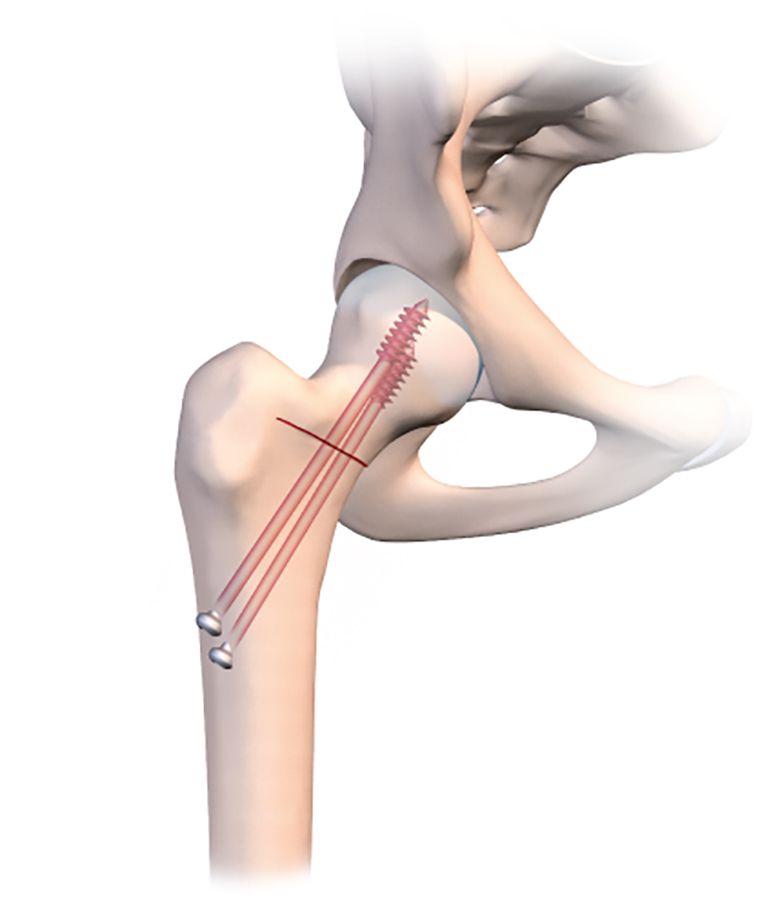

This osteotomy is easy to repair, using the same technique as for a normal badly impacted fracture of the base of the neck of femur, with two or three large diameter cannulated screws.

This makes it much easier to guide a pin into the osteotomy line that has just been created. The pin should of course sit just within the osteotomy line, without going any further. Applying compression will close the line and fix the pin in the neck and head of femur. With the osteotomy line closed and the pin in place, the final stage is to insert a 7mm cannulated screw to stabilize the fixation. A second or even third screw may be used if necessary. The image intensifier should be used to check the correct placement of the screws (Fig. 2e).

However, the fixation process is trickier, because the cannulated screw must not create any new compression which would close the line (Figs. 3b, c, d). I recommend using a large diameter fully-threaded cortical screw as close as possible to the medical cortex into the femoral neck where the bone stock quality is highest. A second more lateral screw will maintain a good degree of compression on the lateral part of the line. In addition, here the screw will embed into the cancellous bone of the greater trochanter.

It is quite possible and even desirable to improve the outcome and avoid any loss of correction upon weight-bearing, to insert a hydroxyapatite wedge into the open line (Fig. 3e).

A wedge could be harvested from the iliac crest in order to fill the gap, but this would be insufficient on its own to produce the desired degree of valgus. When the patient tries to bear weight on the region, the line will be unable to close and crush the wedge. The medial-most fully-threaded screw will be more effective if seated in the lateral cortex of the lateral diaphysis and firmly embedded in the head.